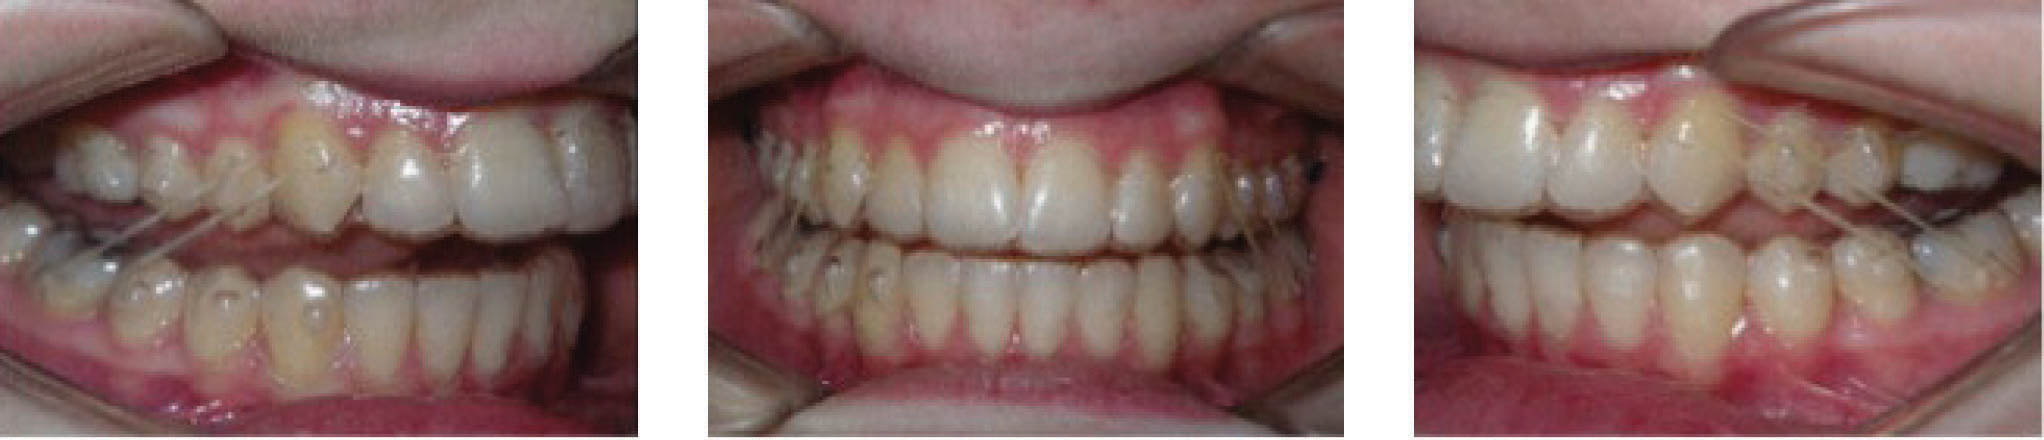

در انتهای درمان (شکلهای 89-۶ الی 91-۶) اکلوژن کلاسI شده است. دندانها مرتب شدند و اوربایت و اورجت طبیعی و به حداکثر زیبایی دست یافتیم. عکس نهایی OPG طبیعی است. مقایسه عکسهای لترال ابتدا و انتهای درمان نشاندهنده تغییر قابل ملاحظه موقعیت انسیزورهای بالا است که منجر به اصلاح اورجت گردیده است. لبخند او عالی گردید.

نتیجه: کل درمان ۲۲ ماه به طول انجامید، 45 الاینر و الاستیک کلاسII ۴ انسی.

شکل 89-6

شکل 90-6

شکل 91-6